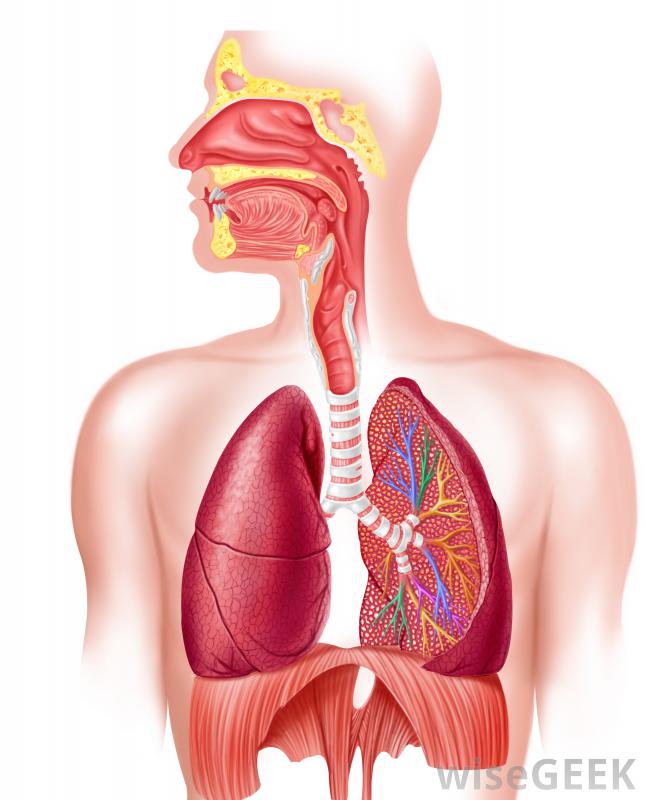

棕色痰是慢性支氣管炎的癥狀明白痰是濃的,粘液有時通過咳嗽排出體外的粘稠物質。它有多種顏色,如白色、黃色、綠色和棕色。與粘液非常相似,事實上,許多專家說,這兩種物質在生物學上是相同的。名稱上的差異往往與人體內各自發生的部位有關,而不是原發性的功能。根據這一認識,痰是發生在呼吸道的粘液,通常由某種刺激物觸發 那些經常吸煙的人可能有褐色的痰。一些粘液或痰幾乎總是存在于咽喉和肺部,是人體移動外來顆粒(如灰塵)的主要方式之一肺部。小顆粒物通常是意外吸入的,將它們排出體外是保持機體效率的一種相對容易的方法。肺的纖毛是排列在肺壁上的細胞,是產生粘液的地方。這些小顆粒物含有毛發狀突起,基本上起到了"掃除"顆粒物的作用

那些經常吸煙的人可能有褐色的痰。一些粘液或痰幾乎總是存在于咽喉和肺部,是人體移動外來顆粒(如灰塵)的主要方式之一肺部。小顆粒物通常是意外吸入的,將它們排出體外是保持機體效率的一種相對容易的方法。肺的纖毛是排列在肺壁上的細胞,是產生粘液的地方。這些小顆粒物含有毛發狀突起,基本上起到了"掃除"顆粒物的作用 暴露在空氣污染中可能會導致褐色痰。人們通常不會注意到自己的痰,也不知道痰的顏色直到有這么多的咖啡因,身體才需要排出一些。當某些東西引起產量增加時,人們常常會咳嗽或吐痰。棕色通常被認為是不尋常的,盡管有許多可能的解釋

暴露在空氣污染中可能會導致褐色痰。人們通常不會注意到自己的痰,也不知道痰的顏色直到有這么多的咖啡因,身體才需要排出一些。當某些東西引起產量增加時,人們常常會咳嗽或吐痰。棕色通常被認為是不尋常的,盡管有許多可能的解釋 呼吸系統對吸煙者吸煙的擔憂是導致褐色痰的最常見原因之一。當人們經常從香煙、雪茄或煙斗中吸食煙霧時,在大多數情況下,吸煙者吸入的不僅僅是尼古丁煙霧,還會吸入一系列的樹脂、焦油和其他化學物質。這些物質往往會被困在肺部。重度吸煙者通常會咳出少量棕色粘液,尤其是在早晨,而且在大多數情況下,這只是肺部正常的一部分清潔自己并排出異物。

呼吸系統對吸煙者吸煙的擔憂是導致褐色痰的最常見原因之一。當人們經常從香煙、雪茄或煙斗中吸食煙霧時,在大多數情況下,吸煙者吸入的不僅僅是尼古丁煙霧,還會吸入一系列的樹脂、焦油和其他化學物質。這些物質往往會被困在肺部。重度吸煙者通常會咳出少量棕色粘液,尤其是在早晨,而且在大多數情況下,這只是肺部正常的一部分清潔自己并排出異物。 那些吸煙的人容易患上棕色痰,因為他們吸收的不僅僅是尼古丁試圖戒煙的人也可能會咳嗽出大量的褐色痰。戒煙后,肺部的纖毛通常會受到損害或至少會因吸煙而減慢,重新開始發揮更充分的潛能。這些細小的毛發狀突起開始清除肺部的大量痰。這一過程可能持續數月接觸二手煙可能會在他們的肺里形成褐色的痰生活在空氣污染嚴重地區的人們也可能不時地咳出褐色的痰。灰塵也可能是一個原因。當打掃一個塵土飛揚的房間或在周圍吹沙子或灰塵時,微小的顆粒可能會被卡在喉嚨里。粘液隨后會被咳嗽出來,由此產生的痰會呈現棕色和顆粒狀。在幾乎所有的情況下,這都是暫時的,一旦停止接觸就會消失。食物和飲料某些食物和飲料會使人的痰呈褐色。這通常是無害的,盡管這可能令人擔憂。巧克力、紅酒和黑蘇打水都會暫時改變一個人痰的顏色感染和健康問題某些呼吸道或肺部感染是更嚴重的原因。通常當一個人得了呼吸道疾病時,肺部將開始產生比正常情況更多的粘液,以捕獲某些細菌和其他異物。例如,棕色痰是慢性支氣管炎的常見癥狀,并且可能出現更嚴重的呼吸道感染,如肺癌或肺氣腫很多事情都有可能造成這種情況,但要想找到確切的病因,幾乎總是需要一位有資格的醫學專家的檢查。任何擔心自己咳出的痰的人,特別是如果問題已經持續了一段時間,通常建議進行體檢以排除更嚴重的情況。